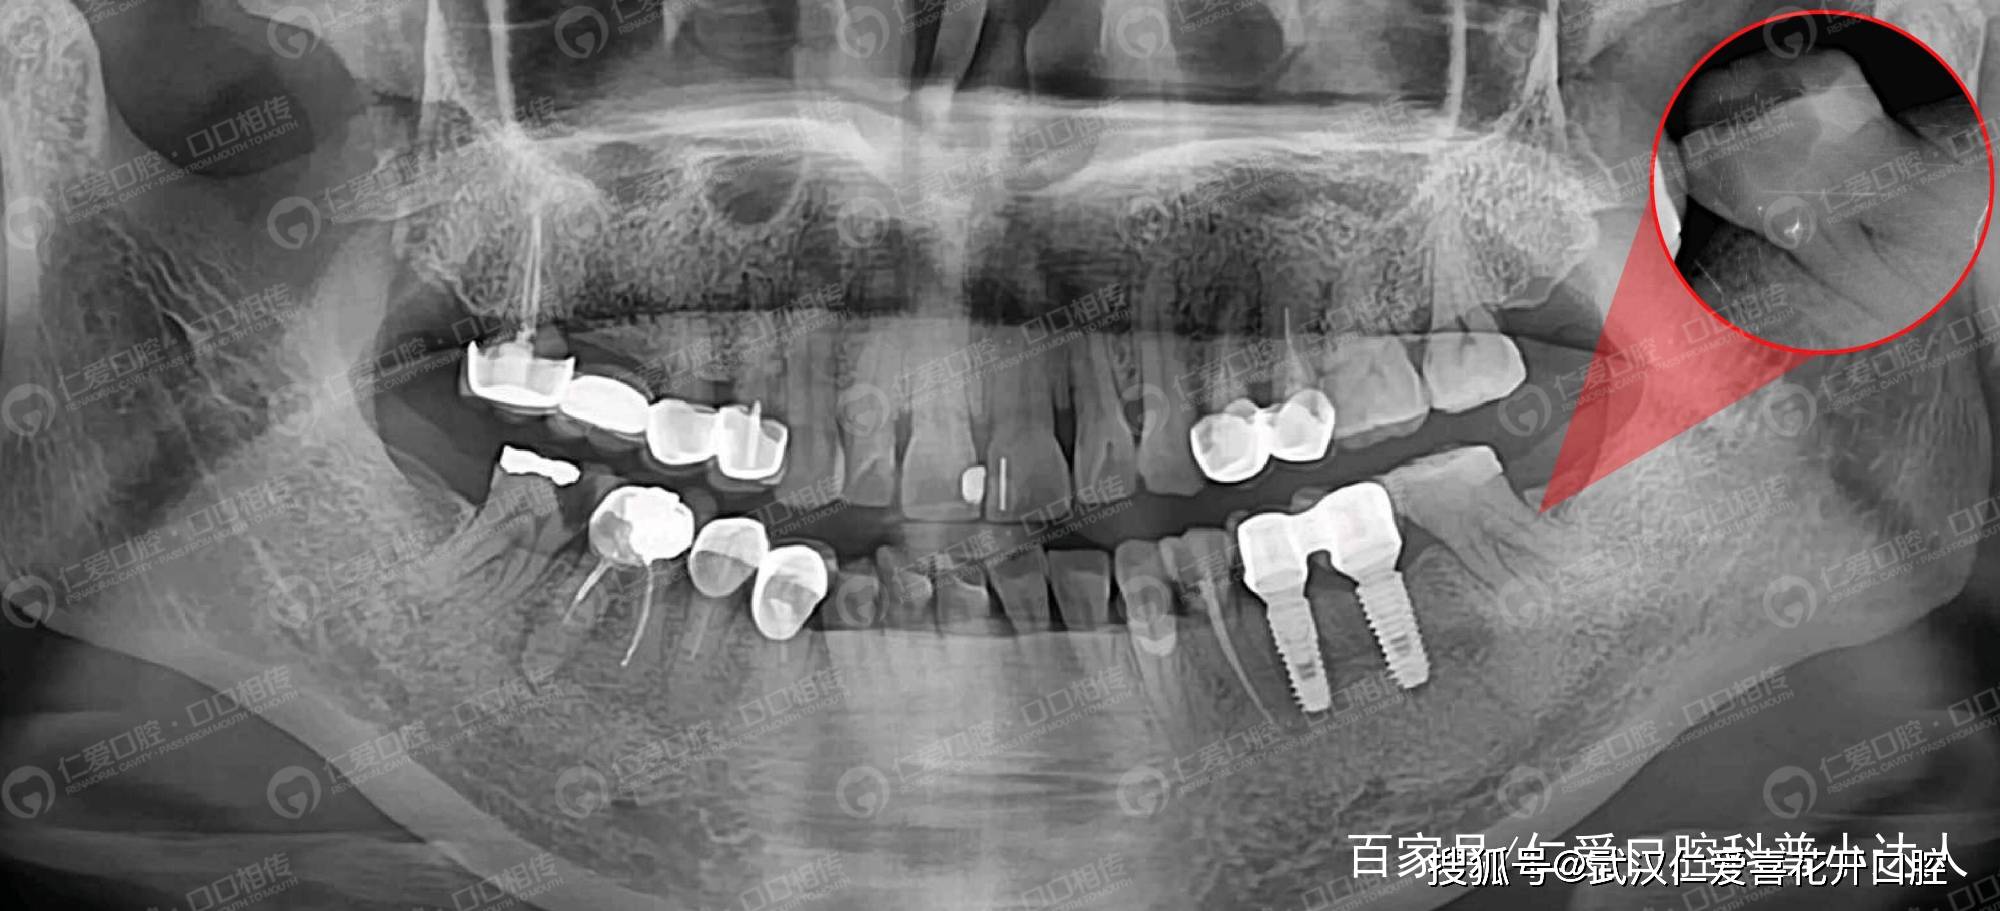

仁爱口腔#医师告诉你:为什么根管治疗要反复拍片?

uu们帮忙看一下根管治疗的片子